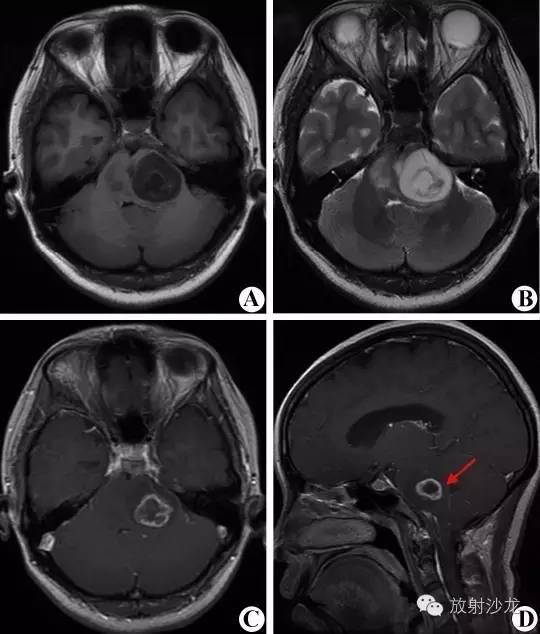

5.3.2脑干肿瘤:右侧桥脑近小脑半球占位。 T1WI(A)呈不均匀等低信号,T2WI(B)呈混杂高信号;增强扫描(C、D)呈不均匀环形强化,壁厚薄不均,第四脑室受压变窄。

桥脑偏左侧占位。T1WI(A)呈不均匀低信号,T2WI(B)呈不均匀高信号。增强扫描(C、D)呈明显不均匀环形强化,第四脑室受压变形。